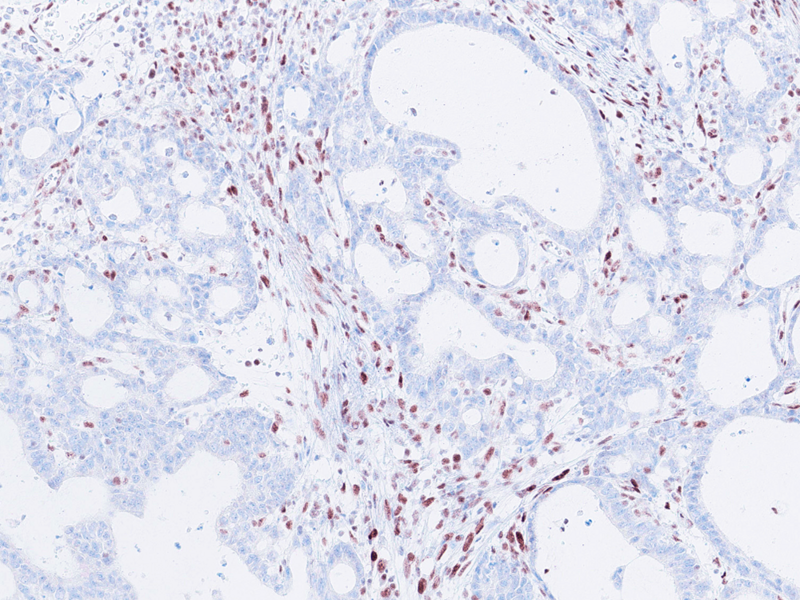

Histologically, the tumour was confirmed to be an adenocarcinoma invading through the gastric submucosa into the muscularis propria (Panel A), showing multiple architectural patterns. While the majority of the lesion displayed a tubular and papillary arrangement of neoplastic cells (Panel B), there were also mucin pools containing floating tumour cells (Panel C), as well as areas of discohesive signet-ring cells (Panel D), so called for their intracytoplasmic mucin droplet that eccentrically displaces the nucleus. The different architectural patterns were not entirely independent of each other nor were they intermingled, but rather arranged side by side (Panel E).

Immunohistochemical analysis of mismatch repair proteins demonstrated loss of MLH1 (Panel F) and PMS2 expression. MSH2 and MSH6 expression were retained.